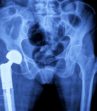

A tout âge on peut être affecté par des maladies des articulations, des os, des tendons, des ligaments ou des nerfs des membres. Il est important de bien comprendre le fonctionnement de son corps et de son anatomie pour mieux pouvoir identifier les symptômes et les causes d’une pathologie localisée et donc, les traitements possibles à envisager.